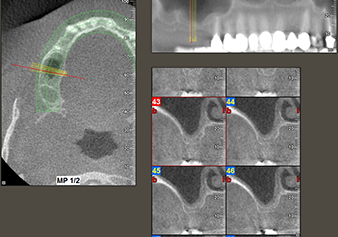

Une patiente de 49 ans, non fumeuse et sans antécédents médicaux remarquables, a été orientée vers notre cabinet de chirurgie orale pour l’extraction chirurgicale de la dent 16 préalable à la pose d’un implant. Après l’extraction, la patiente a rencontré de légers problèmes de sinusite, à la suite de quoi nous avons commencé par attendre six mois avant de prendre la mesure. À l’endroit prévu pour la pose de l’implant, l’os résiduel mesurait 3-4 mm de haut (Fig. 1 et 2).

Situation préopératoire : La crête alvéolaire a bien cicatrisé et la gencive est suffisamment large et kératinisée.

Fig.1 : Situation préopératoire : La crête alvéolaire a bien cicatrisé et la gencive est suffisamment large et kératinisée.

Fig.2 : La DVT montre des dimensions adéquates sur chacune des vues axiale (gauche), latérale (dessus) et transversale (droite). La membrane du sinus maxillaire est encore légèrement épaissie.